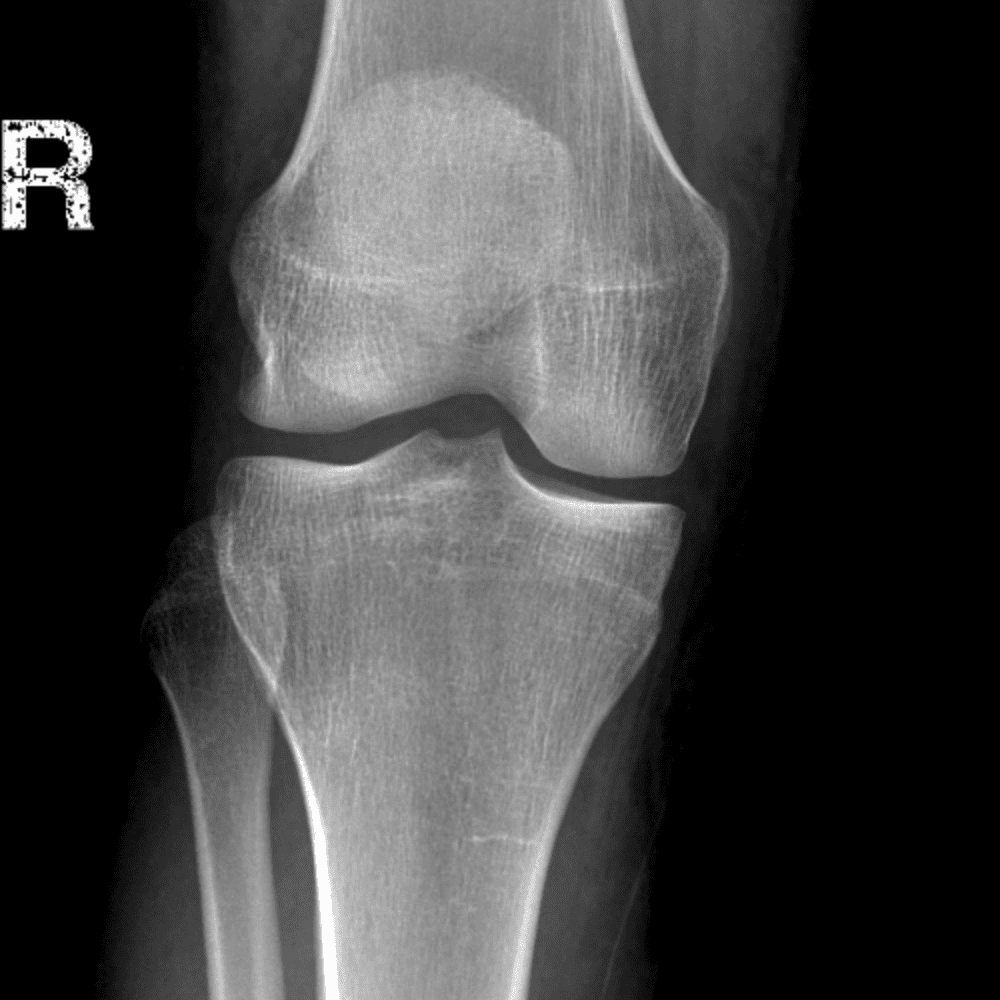

Simula o plantão incluindo casos sutis ou difíceis e alguns normais.